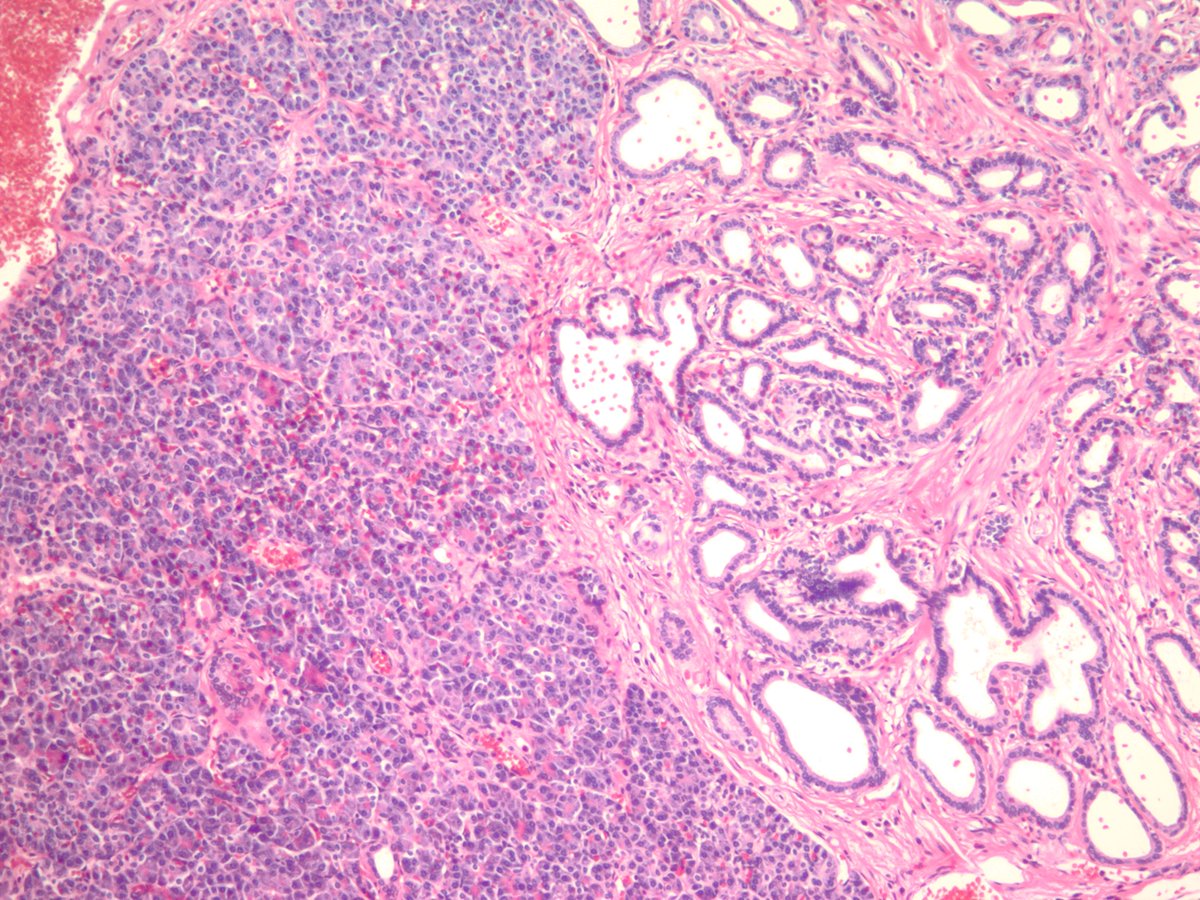

Meckel's diverticulum with pancreatic and gastric heterotopia. #GIpath #pathology

jake_bledsoe's tweet image. Meckel's diverticulum with pancreatic and gastric heterotopia. #GIpath #pathology